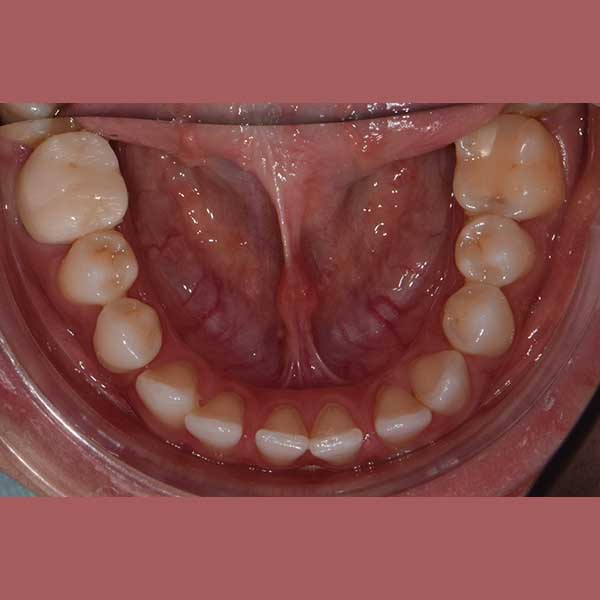

BEFORE

This patient has suffered from spaces between her lower teeth due to an unknown reason, and by examining the teeth, I found that the gums were healthy and fixed braces were installed and the spaces were closed successfully in addition to the paving of the upper teeth successfully as well.